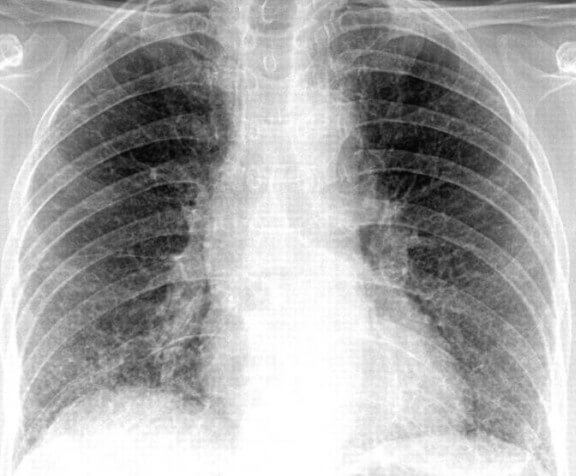

Интерстициальная пневмония – поражения очагового или диффузного характера, протекают с инфильтрацией интерстициальной ткани. У детей данная форма пневмонии вызвана вирусами или пневмоцистами.

На снимке наблюдается увеличение сосудистого пучка и увеличение корней легких. Заметным становится интенсивный силуэт «ветки дерева», что является специфическим признаком болезни.

Фото при интерстициальной пневмонии